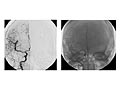

Angiogram of the Head and Neck

An angiogram of the head and neck is an X-ray test that uses a special dye and camera (fluoroscopy) to take pictures of the blood flow in the blood vessels of the head and neck. An angiogram of the neck (carotid angiogram) can be used to look at the large arteries in the neck that lead to the brain. An angiogram of the head (cerebral angiogram) can be used to look at the veins or the four arteries (four-vessel study) carrying blood to the brain.

During an angiogram, a thin, soft tube called a catheter is placed into a blood vessel in the groin or just above the elbow. The catheter is guided to the head and neck area. Then an iodine dye (contrast material) is injected into the vessel to make the area show clearly on the X-ray pictures. The angiogram pictures can be made into regular X-ray films or stored as digital pictures in a computer.

An angiogram can find a bulge in a blood vessel (aneurysm). It can also show narrowing or a blockage in a blood vessel that slows or stops blood flow. An abnormal pattern of blood vessels (arteriovenous [AV] malformation) or abnormal vessels near a tumor can be seen.